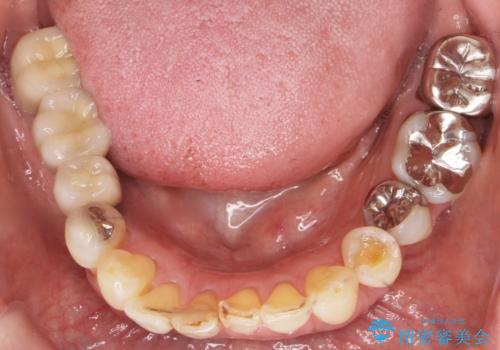

前歯がかけた、ぐらぐらする 60代女性

- 下の前歯が欠けてぐらぐらすることを主訴に来院された患者様です。

以前行った奥歯の治療により下顎前歯の動揺は改善傾向にあり顕著ではなかったのですが、欠けて黒くなっていることと少しの動揺が気になるとのことでした。

元気なうちに治療しておきたいという患者様の強いご希望により、下顎前歯の連結補綴と欠けている小臼歯の補綴治療を行いました。

自然な仕上がりに喜んで下さいました。

クラウンを連結することにより気にされていた動揺もなくなり、安心して頂けました。

被せ物の種類:オールセラミッククラウン スタンダード